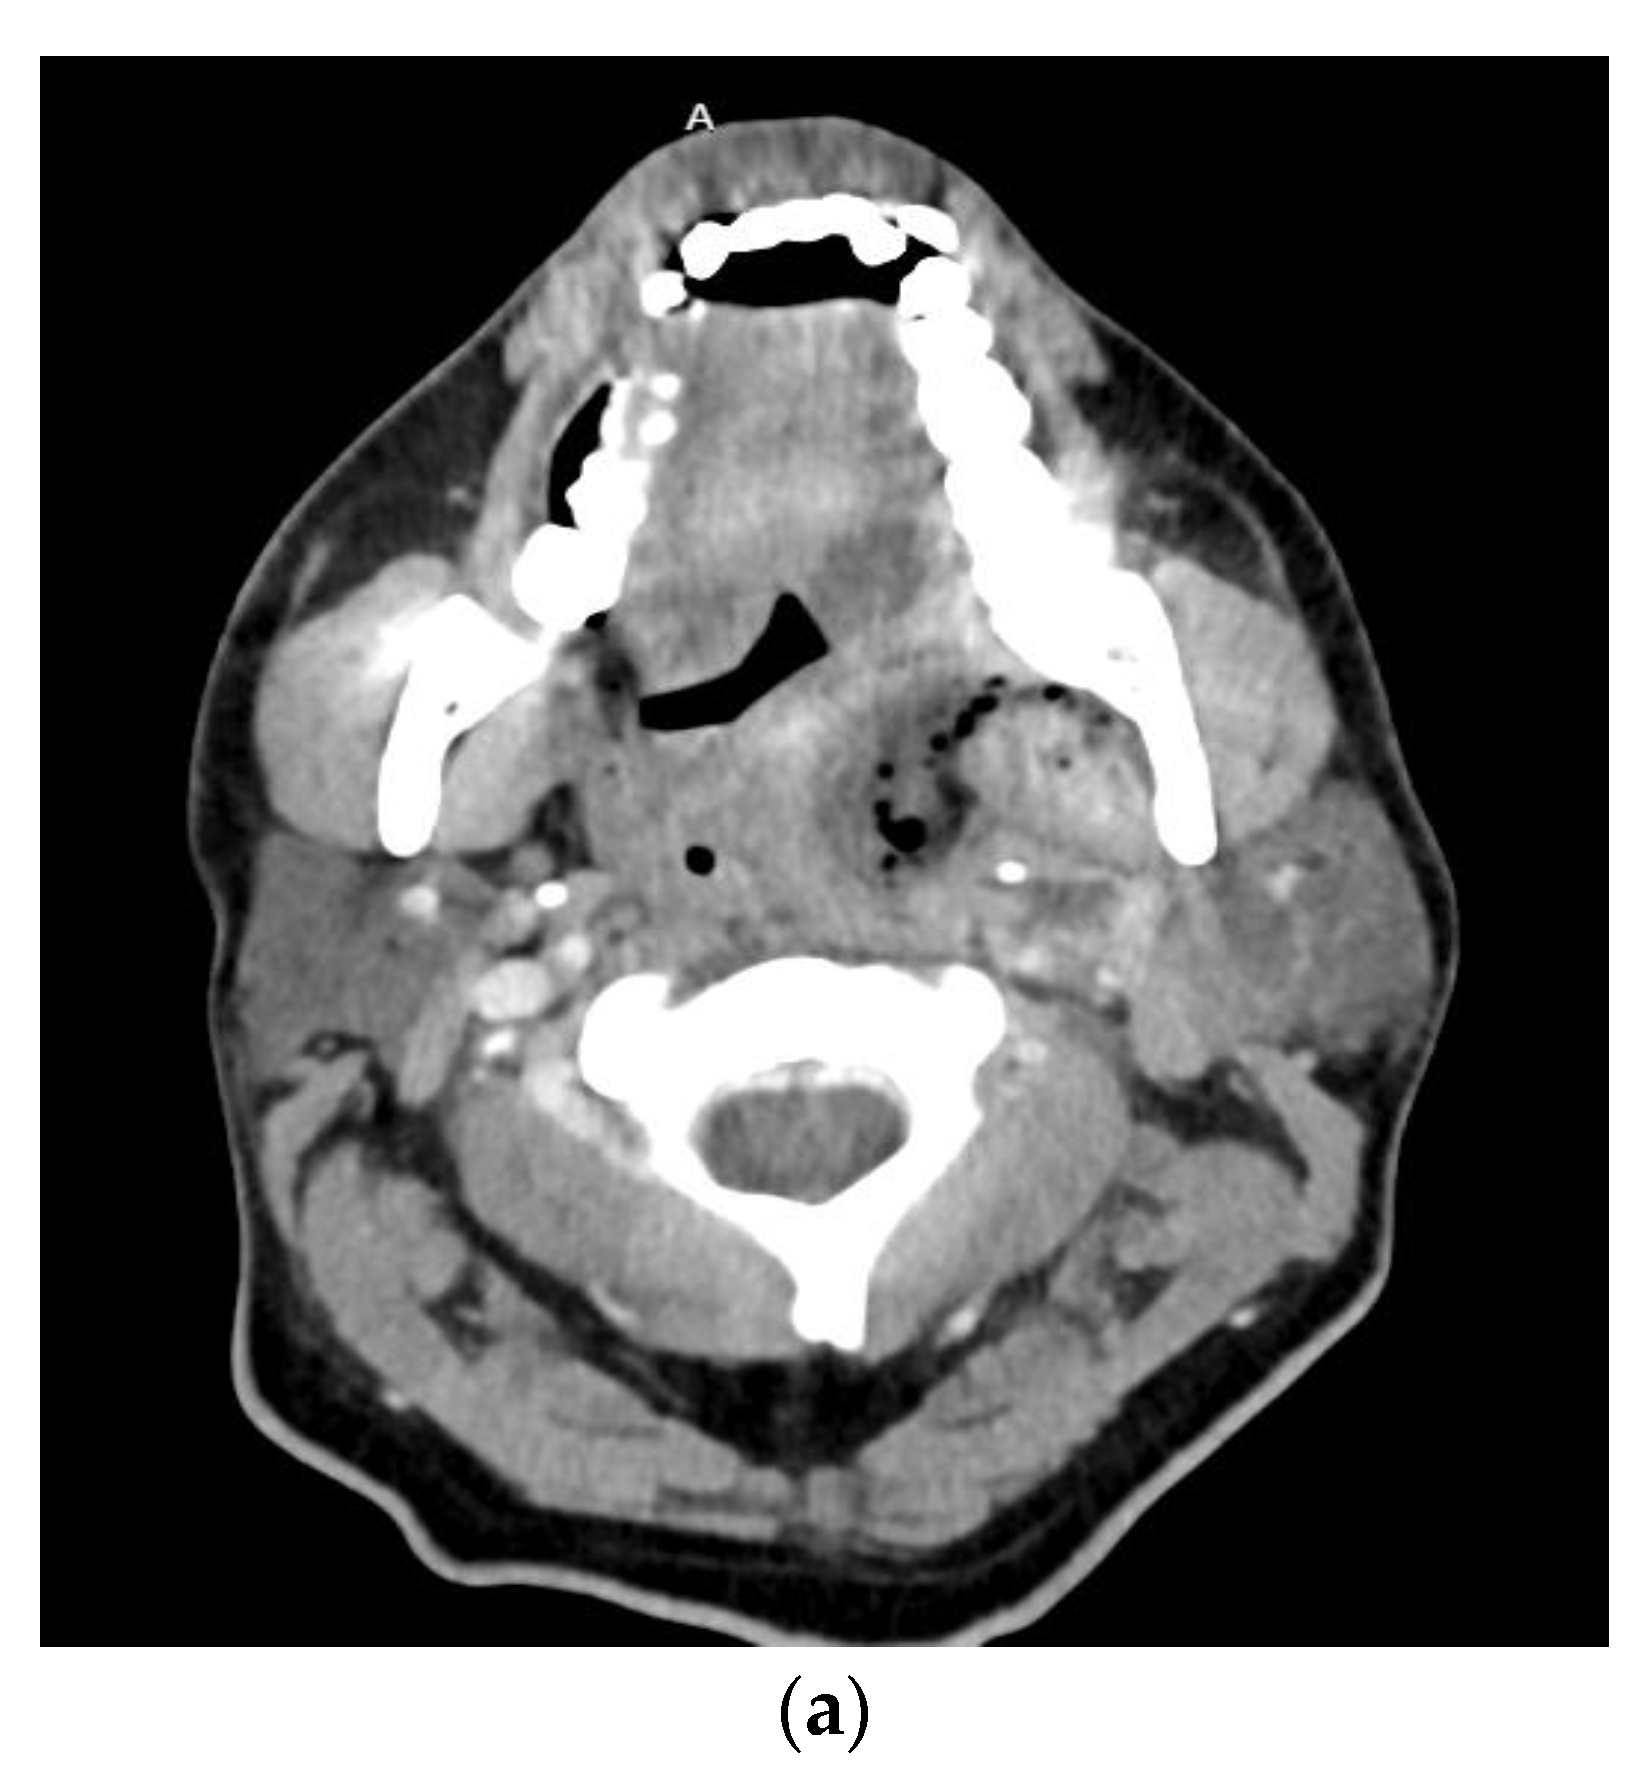

1.3. Descending Necrotizing Mediastinitis

1.4. Orbital Cellulitis, Abscess, and Septic Cavernous Sinus Thrombosis